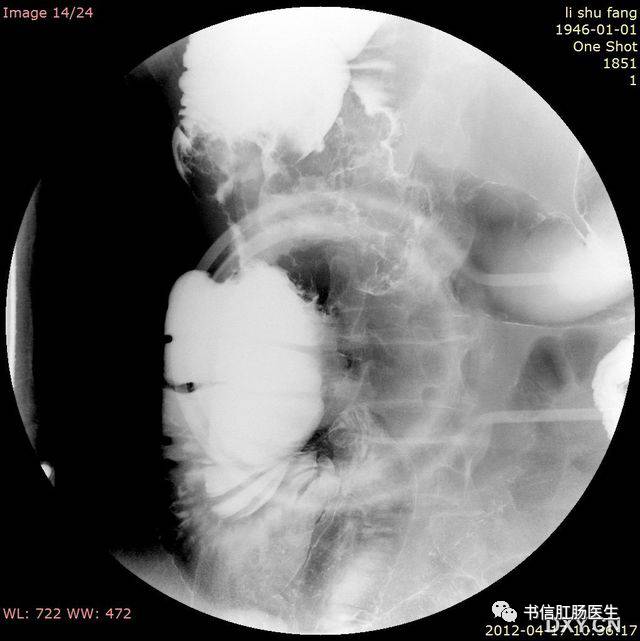

4.双泡征

★ 男婴,14 天,CT 上可见「双泡征」(箭),肠系膜上动、静脉排列正常

■ 影像表现:腹部 X 线平片上表现为上腹部出现 2 个含气囊腔样结构,分别位于左上和中线右侧略偏下,立位可见液气平面,远端无充气或仅有少量充气。该征象还可见于上消化道钡剂或超声检查。

■ 征象解析:双泡征是新生儿或婴儿十二指肠梗阻的特异性表现。十二指肠梗阻时,梗阻近端的十二指肠和胃呈进行性积气、积液并扩张,形成所谓的双泡征。

■ 讨论:双泡征多见于十二指肠闭锁,也可见于十二指肠狭窄、环状胰腺或肠旋转不良等。根据双泡征及其伴随征象可大体判断梗阻的程度及原因,若双泡较大且远端充气,则提示十二指肠完全梗阻(十二指肠闭锁);双泡较小且远端有或多或少的充气,则多为不全梗阻(肠旋转不良、十二指肠狭窄、环状胰腺等)。

另外,当不全性梗阻因气体未进入梗阻远端或梗阻远端少量充气被肠壁吸收,可表现为单纯的双泡征。另一方面,当双泡征远端肠管充气时,并不能排除完全梗阻的可能,因十二指肠闭锁合并胆管发育异常时,梗阻近端气体可通过异常胆管进人梗阻远端。因此,在判断十二指肠梗阻程度时,不能依赖于梗阻远端有无充气。而应全面观察,综合分析,必要时行钡剂或超声检查。